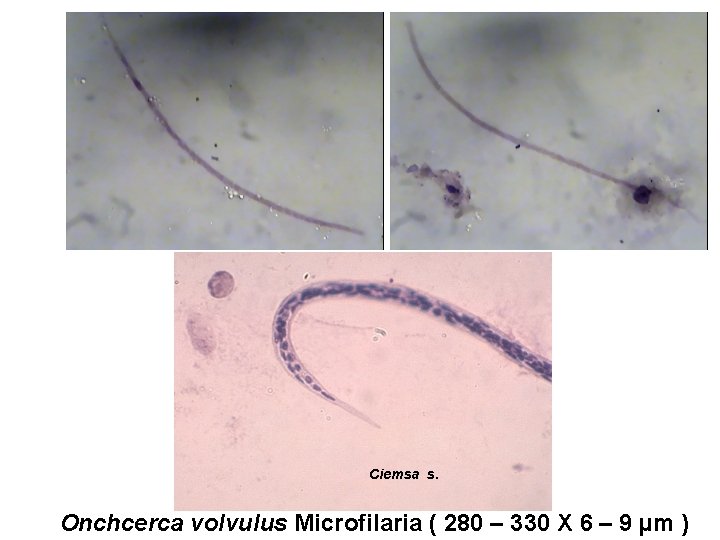

B- Onchocerca volvulus: unsheathed microfilaria long cephalic space short tail Aseptete nuclei.

Ciemsa s. Onchcerca volvulus Microfilaria ( 280 – 330 X 6 – 9 µm )